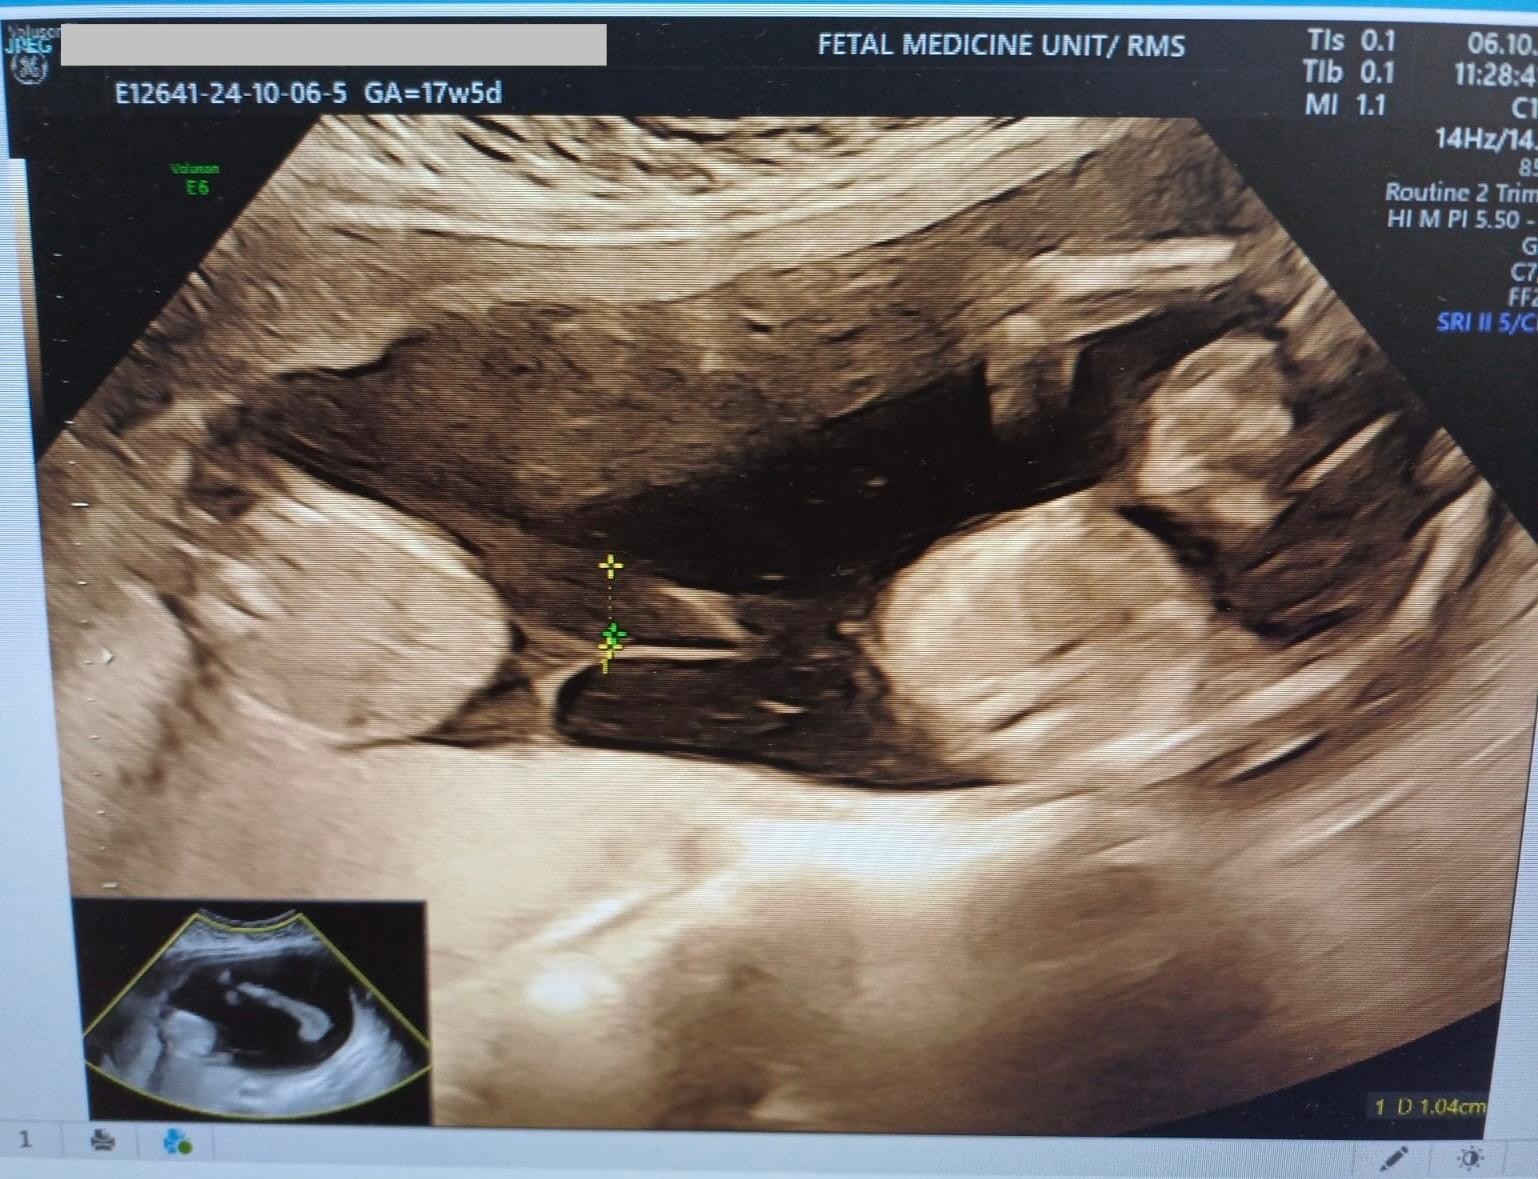

أجرى فريق طب الجنين في دائرة النسائية والتوليد بالخدمات الطبية الملكية عملية نوعية لفصل المشيمة الأحادية باستخدام تقنية الليزر (Fetoscopic Laser Ablation).

وأكد الفريق الطبي أن العملية تكللت بالنجاح، حيث تمكن الحمل من الوصول إلى 37 أسبوعاً و4 أيام دون أي مضاعفات تذكر، مشيراً إلى أن هذه العمليات تصنف ضمن التدخلات الطبية المعقدة والدقيقة التي تتطلب خبرات متقدمة وكوادر مؤهلة على أعلى المستويات.